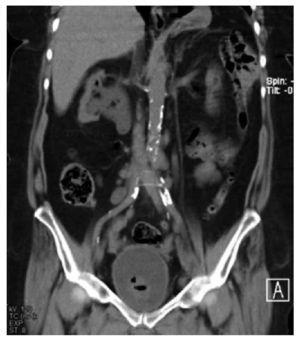

Se ingresó por hematuria macroscópica, anemizante, formadora de coágulos amorfos y dolor cólico nefrítico bilateral, náuseas y vómitos, además de una respuesta inflamatoria sistémica manifestada por mal estado general, cuadros de hipertermia e hiporexia. En los exámenes de laboratorio tenía leucocitos totales de 12 400, hemoglobina 10.3 g/dL, hematocrito 31.1, plaquetas 441 000, glucosa 140 mg, urea 117.1 mg/ dL, nitrógeno ureico 55.0 mg/dL, creatinina 3.0 mg/dL, cloro 106 mmol/L, potasio 4.5 mmol/L, sodio 130 mmol/L, urocultivo positivo a Escherichia coli. En imágenes, desde la placa simple de tracto urinario se observaba la presencia de gas en topografía ureteral, siendo más evidente en el tercio superior de uréter derecho. En la tomografía se observaron signos de pielonefritis enfisematosa bilateral, caracterizada por colección de gas en cavidades renales izquierdas y en el parénquima renal del polo superior derecho, así como en uréter de manera bilateral, con ureteropielocaliectasia bilateral sin presencia de imágenes hiperdensas relacionadas a litos. En cortes coronales, se observó la ureteropielocaliectasia en la zona por donde se cruza el uréter con la vena ovárica de manera bilateral.

El caso que presentamos es una paciente con infección de vías urinarias complicada en pielonefritis enfisematosa bilateral, secundaria a uropatía obstructiva por la vena ovárica bilateral, por lo anterior tiene la particularidad de estar en el 11% de la presentación general, ya que dentro de los estudios de imagen no se evidenció la presencia de otro proceso obstructivo que condicionara la ureteropielocaliectasia y por consiguiente, el proceso enfisematoso. El cuadro clínico fue muy inespecífico, y la paciente fue ingresada por complicación de una pielonefritis enfisematosa. En la Figura 1, se observa un proceso enfisematoso en el uréter en el tercio proximal derecho. En la Figura 2, se observa ectasia bilateral con gas en parénquima renal en el polo superior derecho y en las cavidades del riñón izquierdo, así como el uréter del mismo lado, también se alcanza a observar la presencia de una escotadura en el uréter superior izquierdo y algo del derecho, justo por debajo de la unión ureteropiélica, que es el lugar donde se cruza con la vena ovárica.

Figura 2. Ectasia bilateral con gas en parénquima renal polo superior derecho y en cavidades de riñón izquierdo, así como del uréter del mismo lado, presencia de escotadura en uréter superior izquierdo y del derecho, justo por debajo de la unión ureteropiélica, donde se cruza con la vena ovárica.

En la Figura 3 se observa como la vena ovárica izquierda ingresa a la vena renal ipsilateral, produciendo ectasia ureteral desde el cruce de las ilíacas, se demuestra que es el sitio donde se cruza el uréter y la vena ovárica, allí se manifiesta la escotadura antes mencionadas, también demostrándose en esta figura la ectasia derecha con gas parenquimatoso hacia el polo superior. En la Figura 4 resalta del lado derecho, justo donde se cruza la vena ovárica con el uréter es donde se produce la ectasia a nivel de la bifurcación de la aorta en ilíacas primitivas, y del lado izquierdo en el cruce ureteral con los vasos ilíacos nuevamente se cruza con la vena ovárica produciendo ectasia.

Figura 3. Vena ovárica ingresando por la vena renal izquierda ipsi-lateral, produciendo ectasia ureteral desde el cruce de los ilíacos. Se demuestra sitio donde se cruza uréter y vena ovárica, allí se manifiesta la escotadura antes mencionada. También se observa ectasia derecha con gas parenquimatoso hacia polo superior.